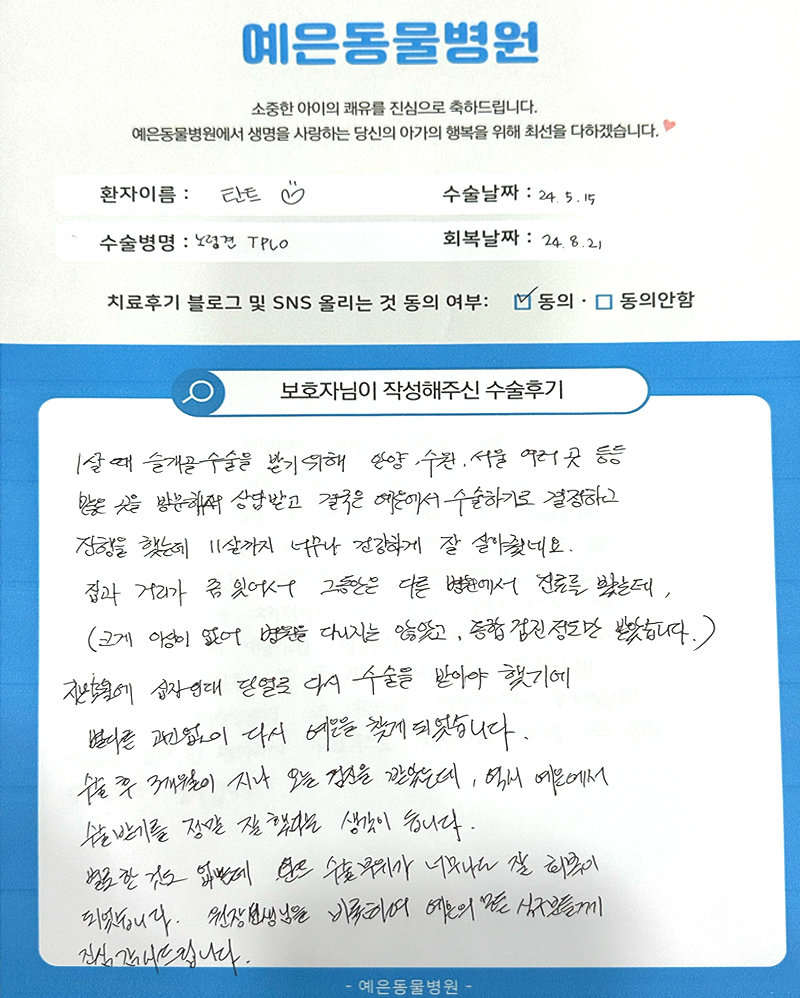

직접 작성해주신

정형외과 수술 후기 모음

돋보기를 눌러 크게 확인해보세요.

보호자님들이

직접 작성해주신

정형외과 수술 후기 모음

돋보기를 눌러 크게 확인해보세요.